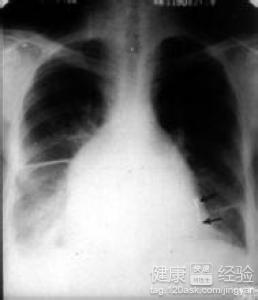

1當患者的心肌出現了肥厚的情況時,可以稱為肥厚性的心肌性疾病,通常患者的左邊心室會有左心室流出道有無梗阻可分為梗阻性和非梗阻性肥厚型心肌病,不對稱性室間隔肥厚致主動脈瓣下狹窄者稱特發性肥厚型主動脈瓣下狹窄。

3通常患有了該病後,是不會傳染給他人的,但是該病具有一定的遺傳因素,可以導致家族中多人發病。目前治療首選采取手術進行治療,合並嚴重二尖瓣關閉不全者,可做二尖瓣置換術。